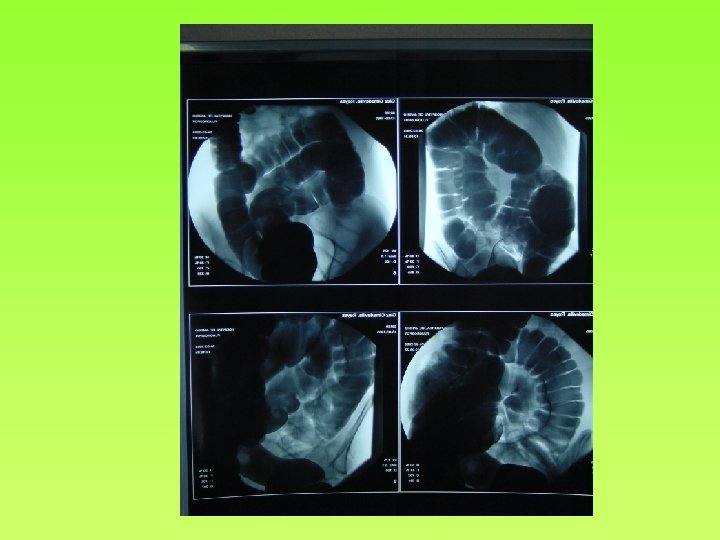

Tiempo de Tránsito Colónico (TTC) con marcadores radiopacos • • • No invasiva Sencilla Se ingieren 24 -50 marcadores radiopacos y se hacen Rx simple 3 y 5 días después, contando los marcadores que hay en cada segmento Dx: Inercia cólica Moreno-Osset E y cols. Estudio del tiempo de tránsito colónico (segmentario y total) en sujetos sanos y pacientes con estreñimiento crónico idiopático Med Clin 1992; 98: 201 -206